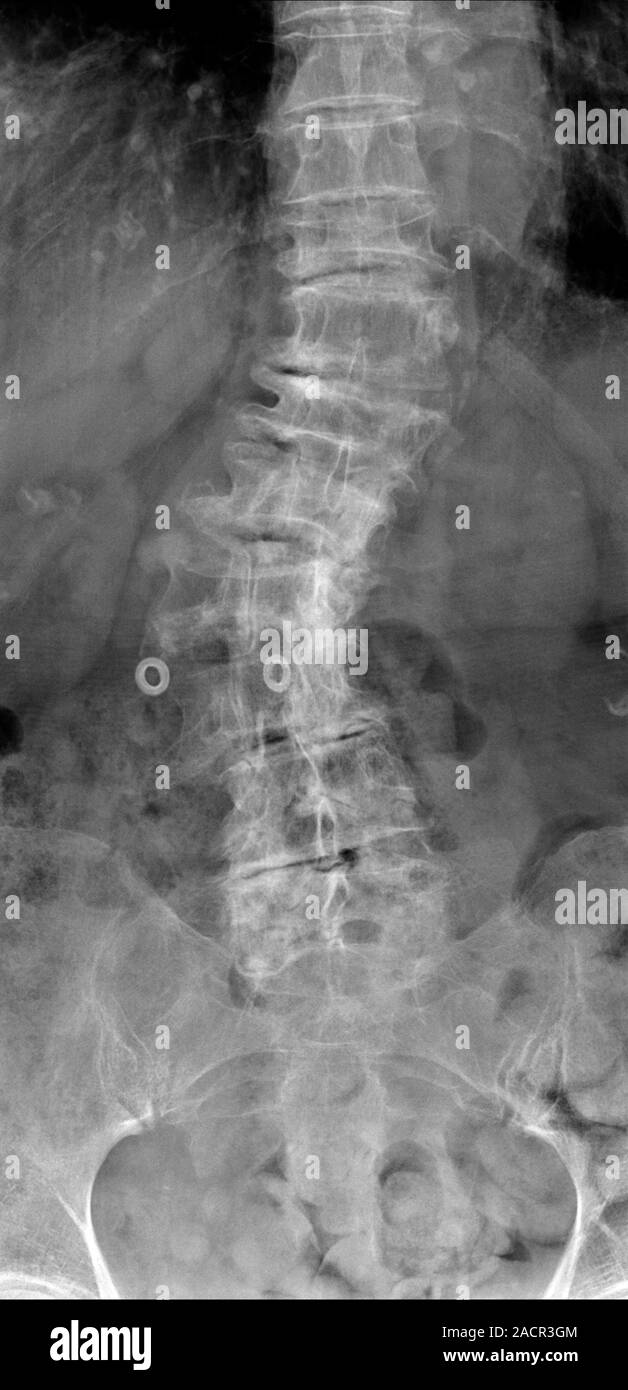

From www.alamy.com

Osteoporosis of spine. Coloured Xray of the lower back of a patient Brittle Bones Xray Signs and symptoms may range from mild to severe. A child born with oi may have soft bones that break (fracture) easily, bones that are not formed normally, and other problems. Osteogenesis imperfecta (oi), also known as brittle bone disease or brittle bone dysplasia, most commonly presents in children. It is also known as brittle bone disease. Osteoporosis causes bones. Brittle Bones Xray.